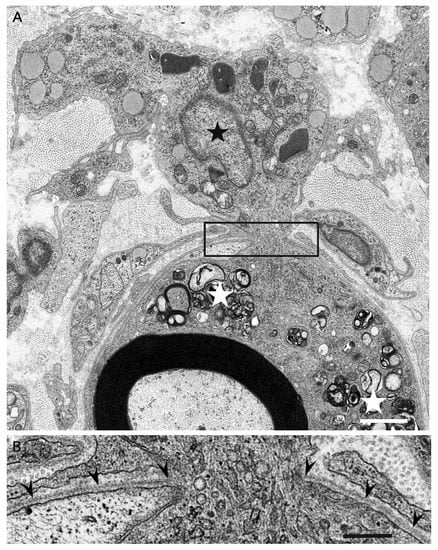

- Koike, H.; Nishi, R.; Ikeda, S.; Kawagashira, Y.; Iijima, M.; Katsuno, M.; Sobue, G. Ultrastructural mechanisms of macrophage-induced demyelination in CIDP. Neurology 2018, 91, 1051–1060. [Google Scholar] [CrossRef]

- Koike, H.; Fukami, Y.; Nishi, R.; Kawagashira, Y.; Iijima, M.; Katsuno, M.; Sobue, G. Ultrastructural mechanisms of macrophage-induced demyelination in Guillain-Barré syndrome. J. Neurol. Neurosurg. Psychiatry 2020, 91, 650–659. [Google Scholar] [CrossRef]

- Koike, H.; Katsuno, M.; Sobue, G. Deciphering the mechanism and spectrum of chronic inflammatory demyelinating polyneuropathy using morphology. Clin. Exp. Neuroimmunol. 2018, 9, 35–46. [Google Scholar] [CrossRef]

- Koike, H.; Katsuno, M. The role of macrophages in Guillain-Barré syndrome and chronic inflammatory demyelinating polyneuropathy. Neurol. Clin. Neurosci 2021, in press. [Google Scholar] [CrossRef]